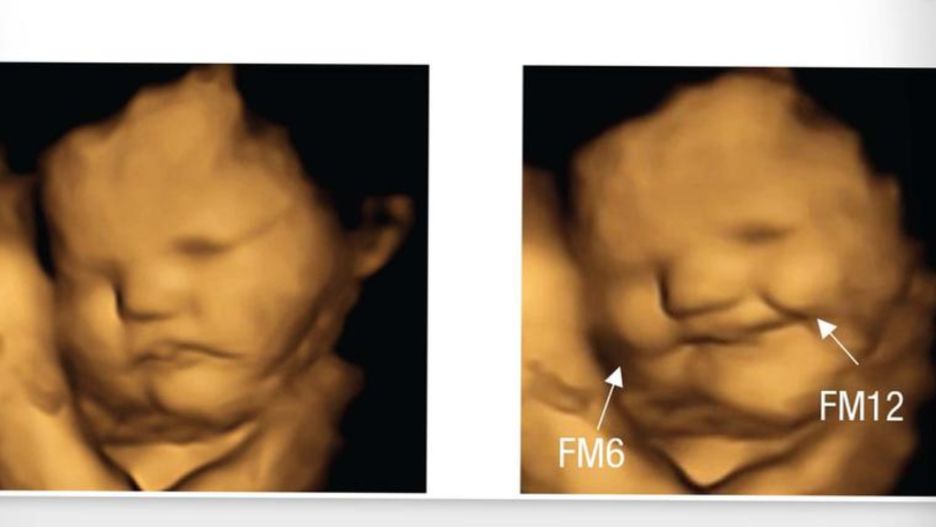

Dzieci w łonie matki zaczynają mieć pierwsze przyzwyczajenia. Grupa naukowców przestudiowała zdjęcia USG, gdzie widać twarze dzieci. Okazało się, że w zależności od tego, co zjadła matka, dziecko miało inną mimikę. Co lubią nienarodzone dzieci, gdy jeszcze znajdują się bezpiecznie pod sercem mamy?

Portal NBC News opublikował wyniki pewnego badania, któremu poddano aż 100 ciężarnych, będących między 32. a 36. tygodniem kobiet. Podawano im kapsułki, które były złożone ze sproszkowanych warzyw i obserwowali reakcję nienarodzonych dzieci. Kobiety dostawały marchew, jarmuż a trzecia grupa była jedynie do kontroli.

Możecie zapytać, dlaczego podawano kapsułki, a nie świeże warzywa i zieleń. Otóż obawiano się, że któraś z matek nie będzie fanką jarmużu, co mogłoby wpłynąć negatywnie na badania. Zjedzenie kapsułki było o wiele szybsze i bardziej miarodajne. Po 20 minutach od spożycia kobiety zostały poddane badaniu USG, gdzie obserwowano reakcję dzieci. Pociechy matek, które zjadły jarmuż, były skrzywione, natomiast w przypadku marchewki dało się zobaczyć delikatny uśmiech. Trzecia grupa, tzw. kontrolna, nie miała żadnych objawów, wszystkie dzieci zachowywały się tak samo. Choć teoria smaku jest dość ciekawa, to nie można jednoznacznie stwierdzić, że maleństwa ulubiły sobie pewien smak już od małego. Być może jest to reakcja mięśni twarzy na gorzki czy też słodki smak.